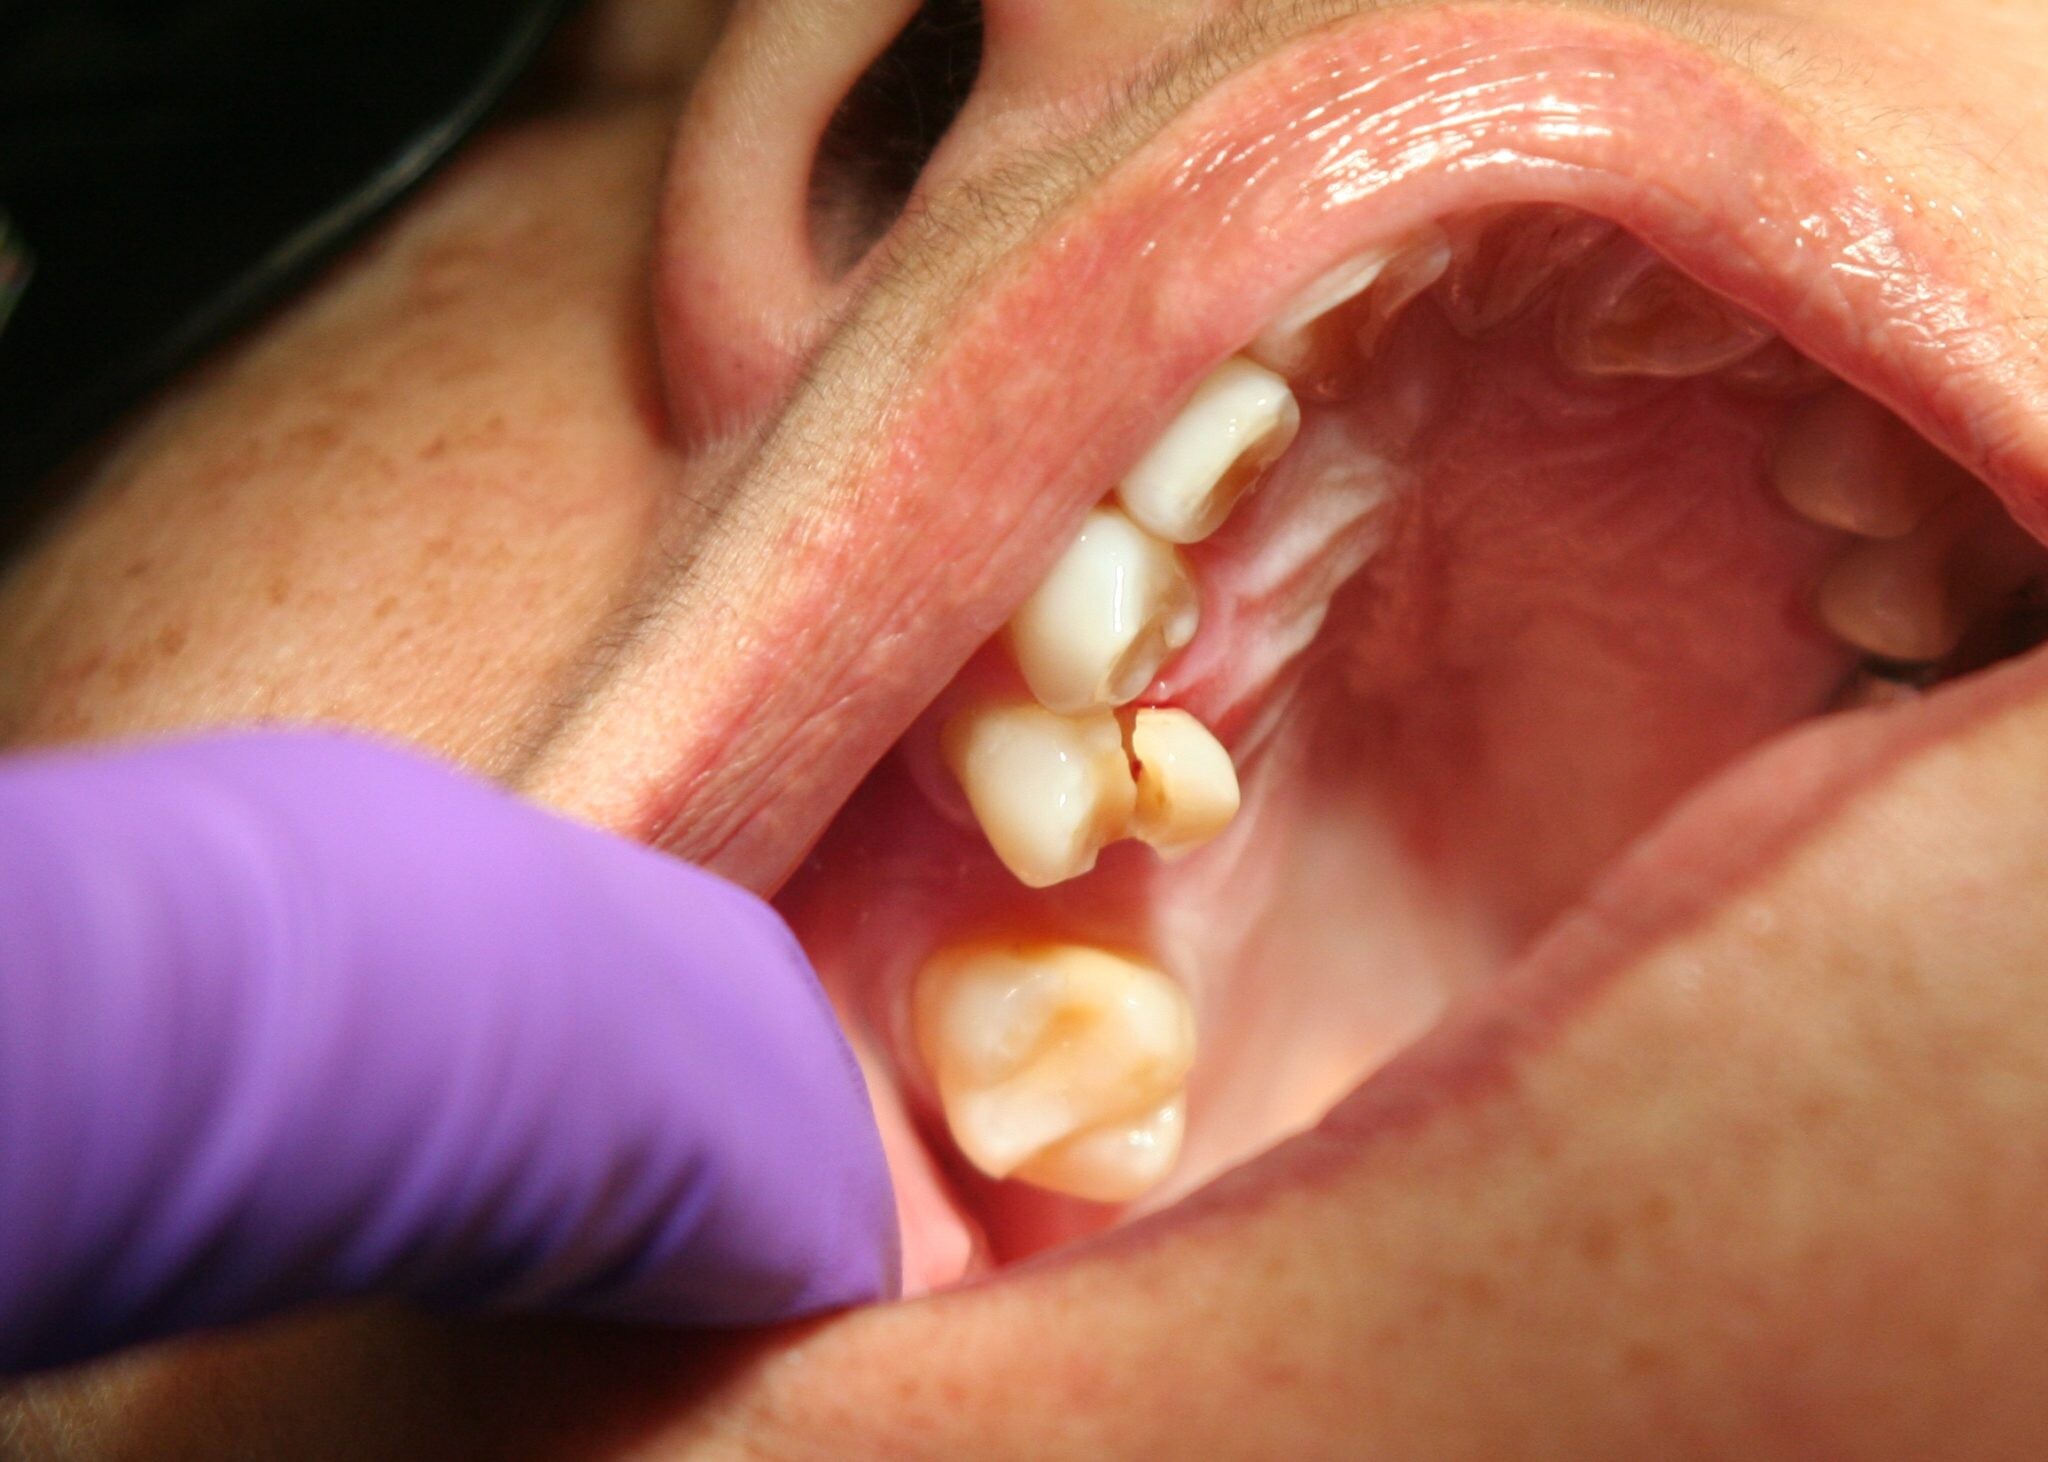

In some cases, jaw pain on one side can indicate underlying oral health problems. Some common issues that cause jaw pain are cavities, an abscessed tooth, gum disease, tooth decay, growth of wisdom teeth, missing or crooked teeth, and clenching or grinding your teeth.

Tooth decay

As tooth decay progresses, it can reach the softer inner layers of the tooth, called dentin and pulp, resulting in sensitivity to hot, cold, or sweet foods and drinks and eventually leading to a toothache. If left untreated, tooth decay can result in an abscess, a painful infection at the root of the tooth that can cause severe pain and swelling. Adhering to your routine dental check-ups, practicing good oral hygiene, and eating a healthy diet can help prevent tooth decay and the resulting toothache.

Abscessed tooth

An abscessed tooth occurs when the pulp inside your tooth becomes infected, typically due to decay or damage. The infection can spread to the tooth’s root and surrounding tissues, causing pain and swelling. In some cases, a pocket of pus may form in the affected area, leading to additional discomfort and even fever. Abscessed teeth may also cause sensitivity to hot or cold foods, a bad taste in your mouth, and difficulty chewing or speaking. If you have an abscessed tooth, inform your provider to prevent further complications and potential tooth loss.

Tooth fracture

The fully impacted or the partially impacted wisdom teeth are at greater risk of tooth decay, than other teeth. This usually happens, because of the location of the wisdom tooth, especially towards the back of the mouth, which is hard to clean. Moreover, since it lies at the back of the mouth, there are chances of food getting easily trapped between the gums and the tooth, promoting the growth of bacteria.